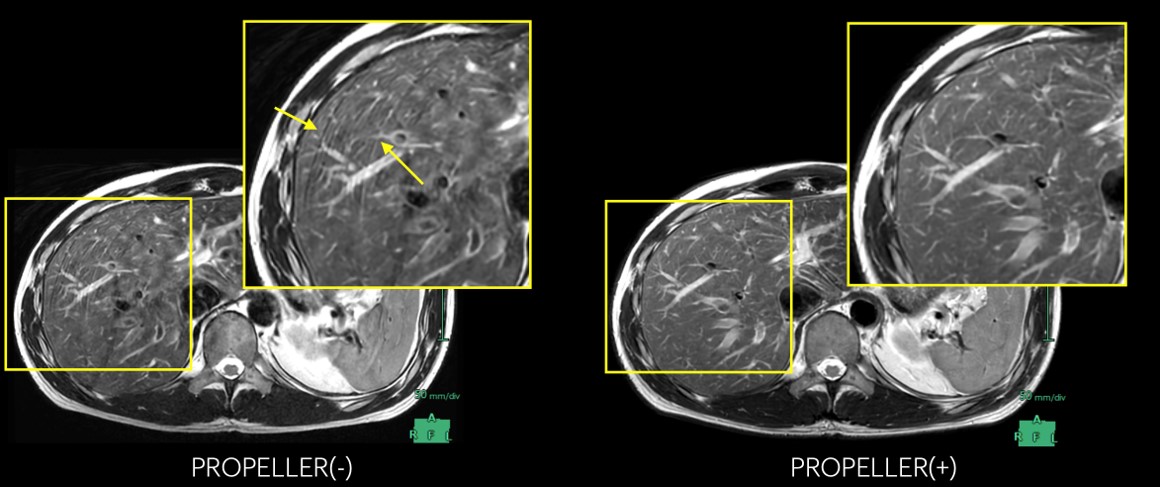

しかし、アーチファクトの中で最も頻繁に発生するモーションアーチファクトは、AIR™ Recon DLによって解消されません。逆にAIR™ Recon DLはノイズのみを除去するので、それに埋もれていたモーションアーチファクトは顕著に目立ってきます。したがって、AIR™ Recon DL導入後は、それまで気にならなかったモーションアーチファクトが目立つようになります。

そこで当院での対策は、PROPELLERを積極的に使用することです。図6に示すように、肝実質内に呼吸によるモーションアーチファクトが混入していますが、PROPELLERを併用することで、アーチファクトが軽減されています。

VictorLiftUpgrade_Kitakyushu09.jpg

図6: 上腹部T2WI  PROPELLERによる体動アーチファクト抑制